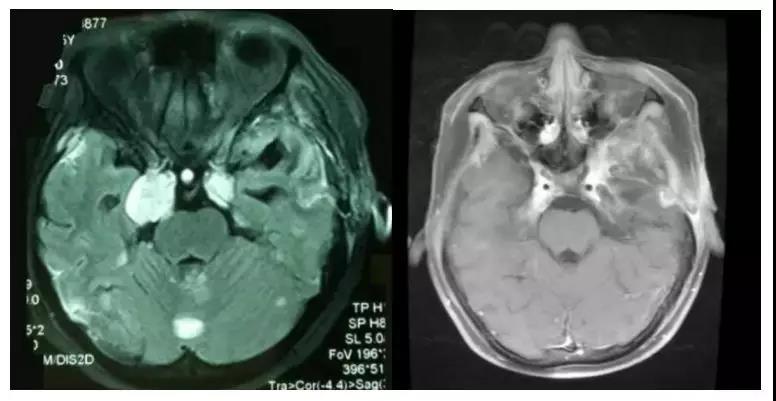

胶质母细胞瘤是星形细胞肿瘤中恶性程度最高的胶质瘤,属WHO Ⅳ级。胶质母细胞瘤可原发于脑实质内,亦可呈继发性。胶质母细胞瘤以手术、放疗、化疗及其他综合治疗为主。虽然对胶质母细胞瘤的综合治疗可暂时缓解病情进展,但不能无进展生存肿瘤,胶质母细胞瘤患者经肿瘤肉眼全切、放疗、化疗等综合治疗后,2年生存率为10%,仅有不到5%的病人可长期生存。对于胶质母细胞瘤患者,除